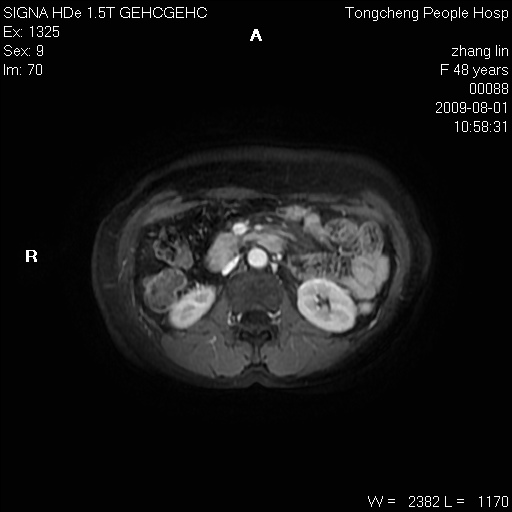

女,48岁。健康体检,彩超发现右肾占位性病变。平素健康。

临床诊断:右肾占位性病变,性质待定(囊肿?肿瘤?)。

上中腹部mr平扫+增强扫描,图像如下:

右肾上极见一类圆形病灶,t1wi呈等信号t2wi呈等高混杂信号,三期增强无强化,边界清---考虑囊肿出血。

同反相位均表现为等信号,病变无强化,考虑含蛋白的囊肿可能,弥散加权相或许有些帮助,